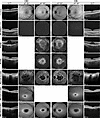

Clinical phenotype of patients.Figure 4

Clinical phenotype of patients. The top panel shows optical coherence tomography (OCT), 30° and 55° fundus autofluorescence (AF) images of a healthy subject (control). The next 3 lower panels show the corresponding images of 3 individuals (P1–P3) with confirmed RPE65-associated retinal disease (RPE65-LCA and RP). P1 shows no AF due to severe RPE65 deficiency. The last 3 panels show the corresponding images of 3 individuals (P4–P6) with confirmed ABCA4-associated retinal disease (STGD1). OD, oculus dexter. OS, oculus sinister.

Optical coherence tomography and autofluorescence imaging. Retinal cross sections were obtained with spectral domain optical coherence tomography (SD-OCT) using the Heidelberg Spectralis OCT (Heidelberg Engineering). Autofluorescence (488 nm) was obtained using the same device.